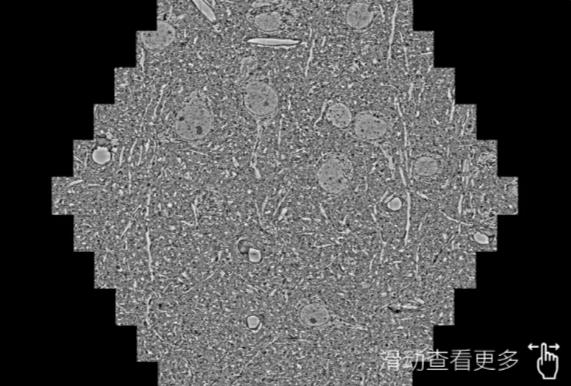

鼠脑切片。左图使用广元蔡司广元扫描电镜MultiSEM706对165μmx143pm面积区域成像,耗时仅需1.5秒。右图为鼠脑切片中30μm区域放大效果。样品由芝加哥大学B.Kasthuri提供。

使用蔡司高速广元扫描电镜MultiSEM对1mm²人脑皮层组织进行高分辨成像,并对其中的各种细胞结构进行三维重构分析。左图展示了2x3mm²组织平面中锥体神经元的三维重构效果。右图显示了局部体积神经元三维重构。图像由哈佛大学chtman实验室提供,渲染图由D. Berger 制作。